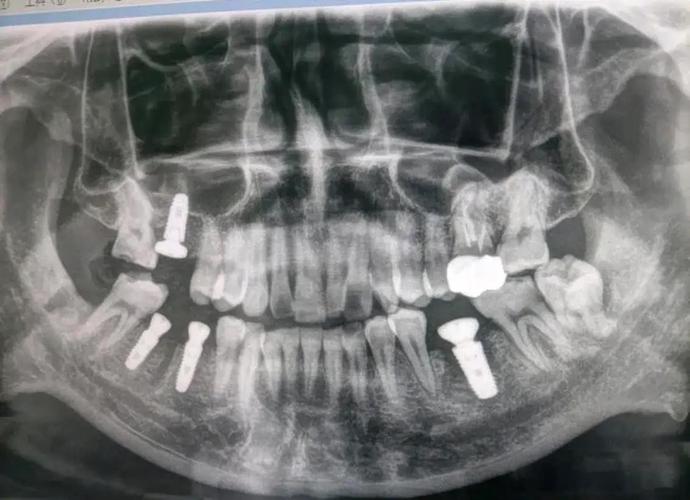

(1)口腔全景片(曲面断层片,Panoramic Radiography, PANO)

- 原理:通过X线球管和胶片同步旋转,一次性拍摄全口牙齿、牙槽骨、颌骨及周围结构的二维影像。

- 优势:视野广,可观察全口牙列、牙槽骨整体情况,操作简单、辐射剂量低(约0.007mSv,相当于1/10次胸片),价格便宜(约100-200元)。

- 局限性:二维成像,存在影像重叠(如上下牙槽骨重叠),无法精确测量骨厚度、密度,对细微骨缺损或神经管位置的判断准确性有限。

- 适用场景:初步筛查、简单牙列缺损(如单颗后牙缺失,骨量充足)、无复杂病史(如无上颌窦炎、无颌骨手术史)的患者。

(2)锥形束CT(Cone Beam Computed Tomography, CBCT)

- 原理:通过锥形X线束围绕患者头部旋转360°,获取三维影像数据,可重建出牙槽骨、神经、血管等结构的立体图像。

- 优势:三维成像,分辨率高,可精确测量骨高度、宽度、密度(误差≤0.1mm),清晰显示下颌神经管、上颌窦、鼻底等解剖结构的位置及与种植体的距离,是目前种植术前评估的“金标准”。

- 局限性:辐射剂量高于全景片(约0.1-0.3mSv,相当于3-5次胸片),价格较高(约300-800元),对金属伪影(如金属冠、种植体)敏感,可能影响图像清晰度。

- 适用场景:复杂病例(如多颗牙缺失、骨量不足、需植骨或上颌窦提升)、上颌后牙区种植(靠近上颌窦)、下颌后牙区种植(靠近神经管)、有颌骨手术史或外伤史的患者。